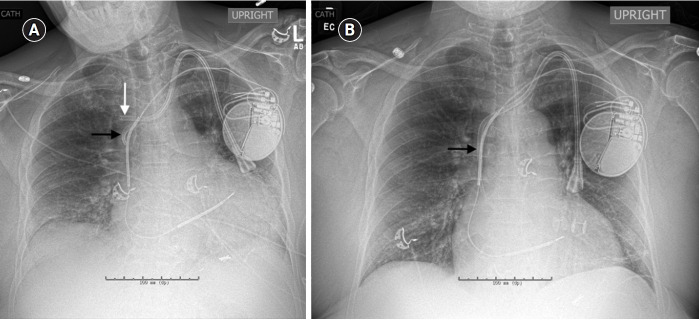

Single-lumen displacement of a hemodialysis catheter into the azygous vein on a chest radiograph.

胸片上血液透析导管向颧静脉的单腔移位。